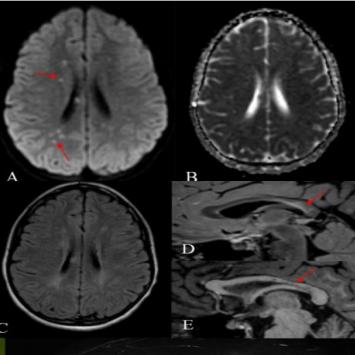

答案:神经梅毒。患者中年男性,急性起病,主要表现为反应迟钝,右下肢软瘫,头颅影像提示以双侧顶枕叶对称性高信号,左侧丘脑点状病灶,额颞叶萎缩。老师们想到了低血糖脑病、PRES、脑梗死、CO中毒等。小僧悟道老师一眼就看出来是梅毒,着实厉害。与年龄不相符的脑萎缩是重要特征。